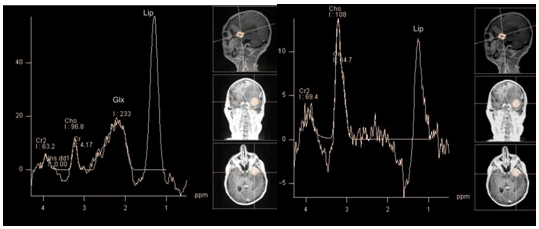

Ischemia: Ischemic stroke or infarction is an acute cerebrovascular accident due to a deficiency of arterial blood flow of the brain, leading to hypoxia and development areas of necrosis. It mainly develops due to occlusion of arterial vessels. The variation in metabolite profile over time gives valuable information for the diagnosis and prognosis of the disease. In the acute phase of infarction its core shows signs of anaerobic metabolism and cell death. Accordingly, spectra from the affected areas are characterized by a high lactate peak, often in combination with significant lipid peaks (Figure 3). Lactate in low concentrations, can also be detected in "penumbra", the area surrounding the core of ischemia. Lactate remains during few weeks the in the affected area.

Figure 3 Super acute infarction. PRESS, TE 30 ms (a) PRESS, TE 135 ms (b) marked decrease in NAA and myo-inositol. High lactate peak.

The slow decrease of NAA concentration in the affected tissue during several days, which can occur even weeks after onset, can't be explained only by destructive action of enzymes on NAA. So, it was suggested, that it is caused by ongoing Ischemia in the affected area. This also may explain the presence of lactate in the core of ischemia in the subacute phase.9 This has important diagnostic value for prognosis, and further treatment (Figure 4).

Figure 4 Infarction, sub acute phase. PRESS, TE 30 ms (a) TE 135 ms (b), lactate concentration map (c) and choline concentration map (d) marked decrease in NAA and myo-inositol (b), the high peaks of lactate and lipids. The map shows that the maximum concentrations of lactate and choline coincide topographically.

Cho level may either increase or decrease in areas of ischemia in the acute and chronic phases.10 Higher concentration of Cho can be explained by gliosis and myelin membranes damage, while its decrease is a result of edema, necrosis and cell death.11